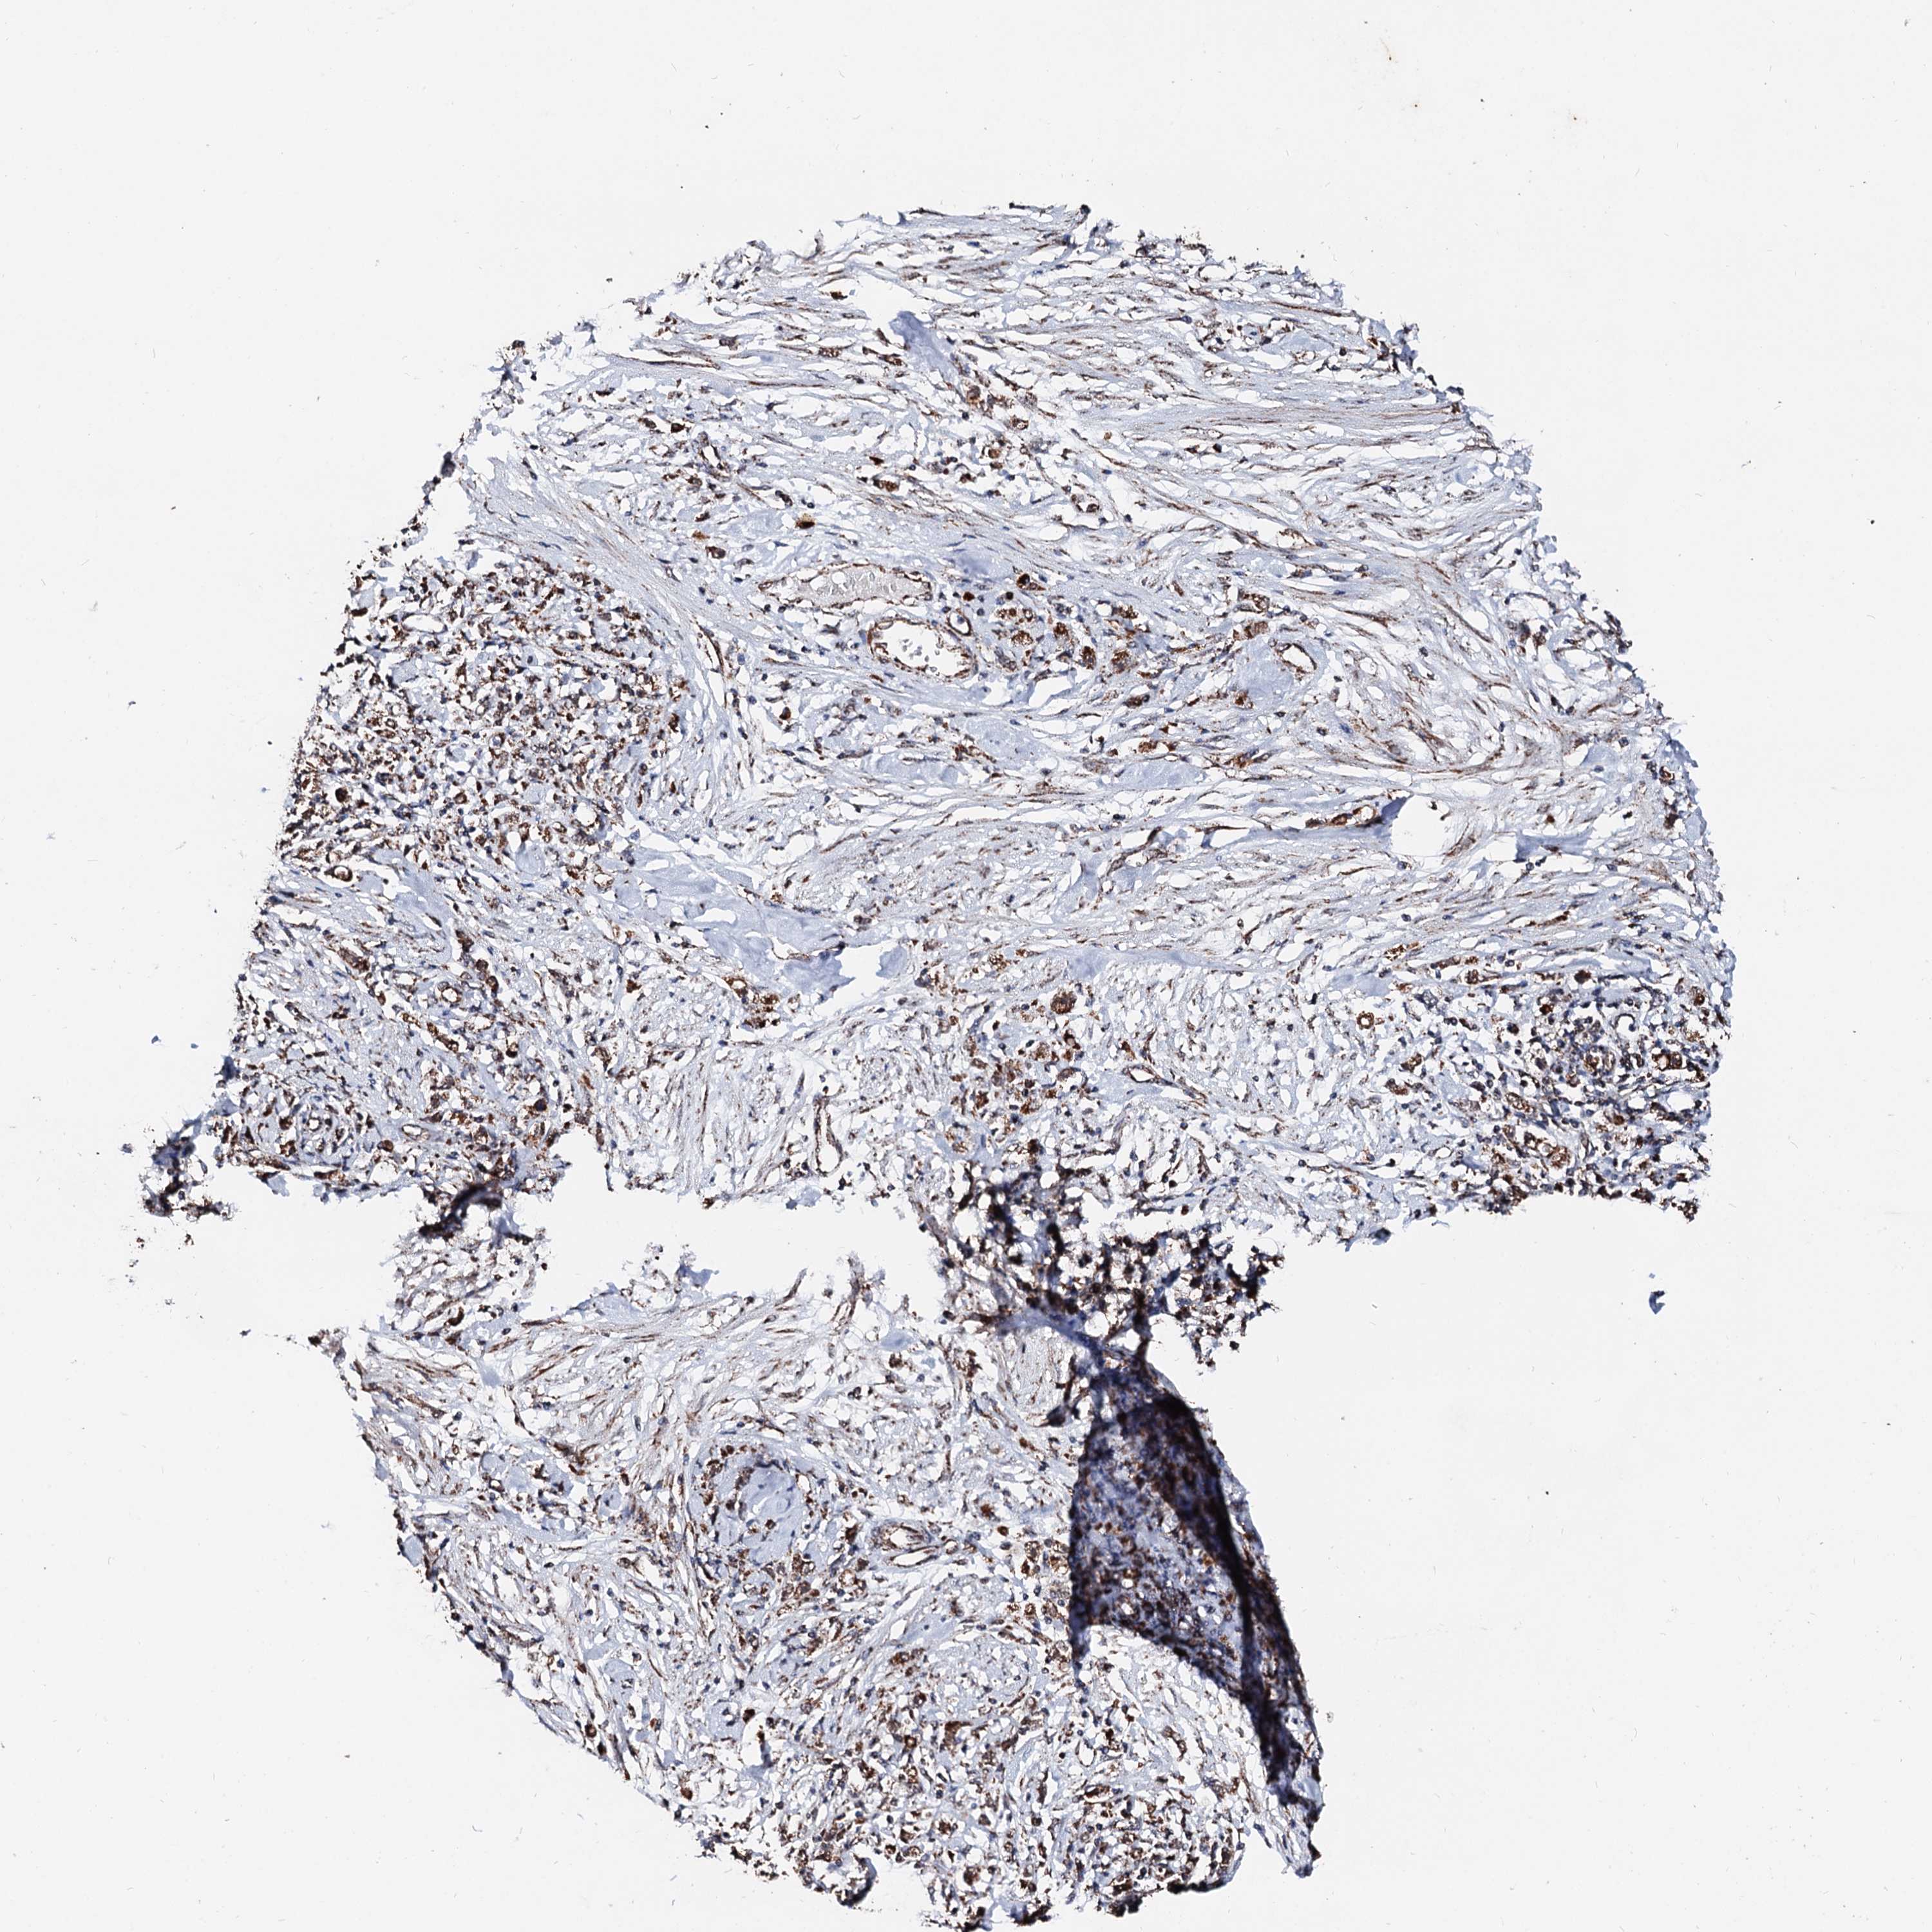

STOMACH CANCER - Protein expressioni

A mouse-over function shows sample information and annotation data. Click on an image to view it in a full screen mode. Samples can be filtered based on level of antibody staining by selecting one or several of the following categories: high, medium, low and not detected. The assay and annotation is described here.

Note that samples used for immunohistochemistry by the Human Protein Atlas do not correspond to samples in the TCGA dataset.

Antibody stainingi

Antibody staining in the annotated cell types in the current human tissue is reported as not detected, low, medium, or high, based on conventional immunohistochemistry profiling in selected tissues. This score is based on the combination of the staining intensity and fraction of stained cells.

Each image is clickable and will lead to virtual microscopy that enables deeper exploration of all samples and also displays staining intensity scores, fraction scores and subcellular localization as well as patient and tissue information for each sample.

Antibody HPA039875

Staining

High

Medium

Low

Not detected

Intensity

Strong

Moderate

Weak

Negative

Quantity

>75%

75%-25%

<25%

None

Location

Nuclear

Cytoplasmic/membranous

Cytoplasmic/membranous,nuclear

Adenocarcinoma, NOS